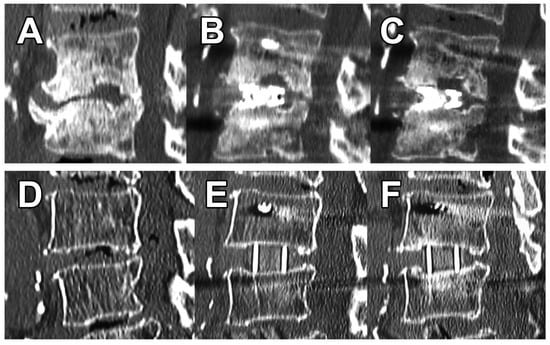

VEC was present in 2 (8.0%) levels for 3DTi vs. 17 (45%) levels for sPEEK (p = 0.002). There were no obvious fractures in either group. At 3 months postoperatively, no levels in the 3DTi group showed VEC progression (Figure 6A–C); however, eight (21%) levels in the sPEEK group showed VEC progression (Figure 6D–F) (p = 0.019). As a result, no levels in the 3DTi group and two (5.3%) levels in the sPEEK group were Marchi classification grade I. Grades II or III were not present in either group. There was also no cage dropout in either group.

Figure 6. Differences in postoperative changes depending on cage. (A), preoperative degenerated interbody; (B), postoperative VEC caused by the 3DTi cage; (C), no further subsidence after 3 months. (D), preoperative; (E), postoperative VEC caused by the sPEEK cage; (F), cage subsidence and decreased lordosis (11° to 6°) after three months.